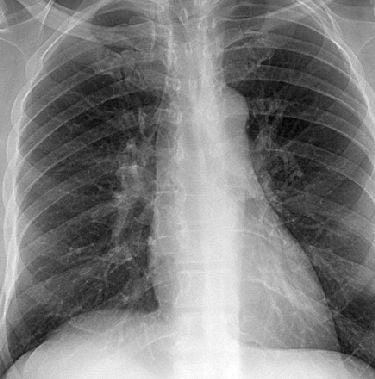

While coronary calcium can be spotted with conventional radiographs, that approach has proved to have poor sensitivity -- around 50% or worse -- in formal studies. The key to radiography's renewed potential is digital technology, which has enabled the utilization of dual-energy techniques with both computed radiography (CR) and digital radiography (DR) systems.

Previous research has shown that single-exposure dual-energy subtraction on a CR system generates a soft-tissue-subtracted image that improves the detection of parenchymal lung nodules. In the latest study, images from a direct DR system (Revolution XR/d, GE Healthcare, Waukesha, WI) were evaluated for detection of coronary artery calcification.

Patient x-rays were taken at 120 kVp and 60 kVp, enabling the routine generation of three images after postprocessing: a standard 120 kVp image, a subtracted soft-tissue image, and a subtracted bone image. In patients with suspected cardiac calcification on the low-energy bone image, the radiologist was asked to rate visualization of coronary calcification on that image compared to the standard posteroanterior and lateral radiographs.